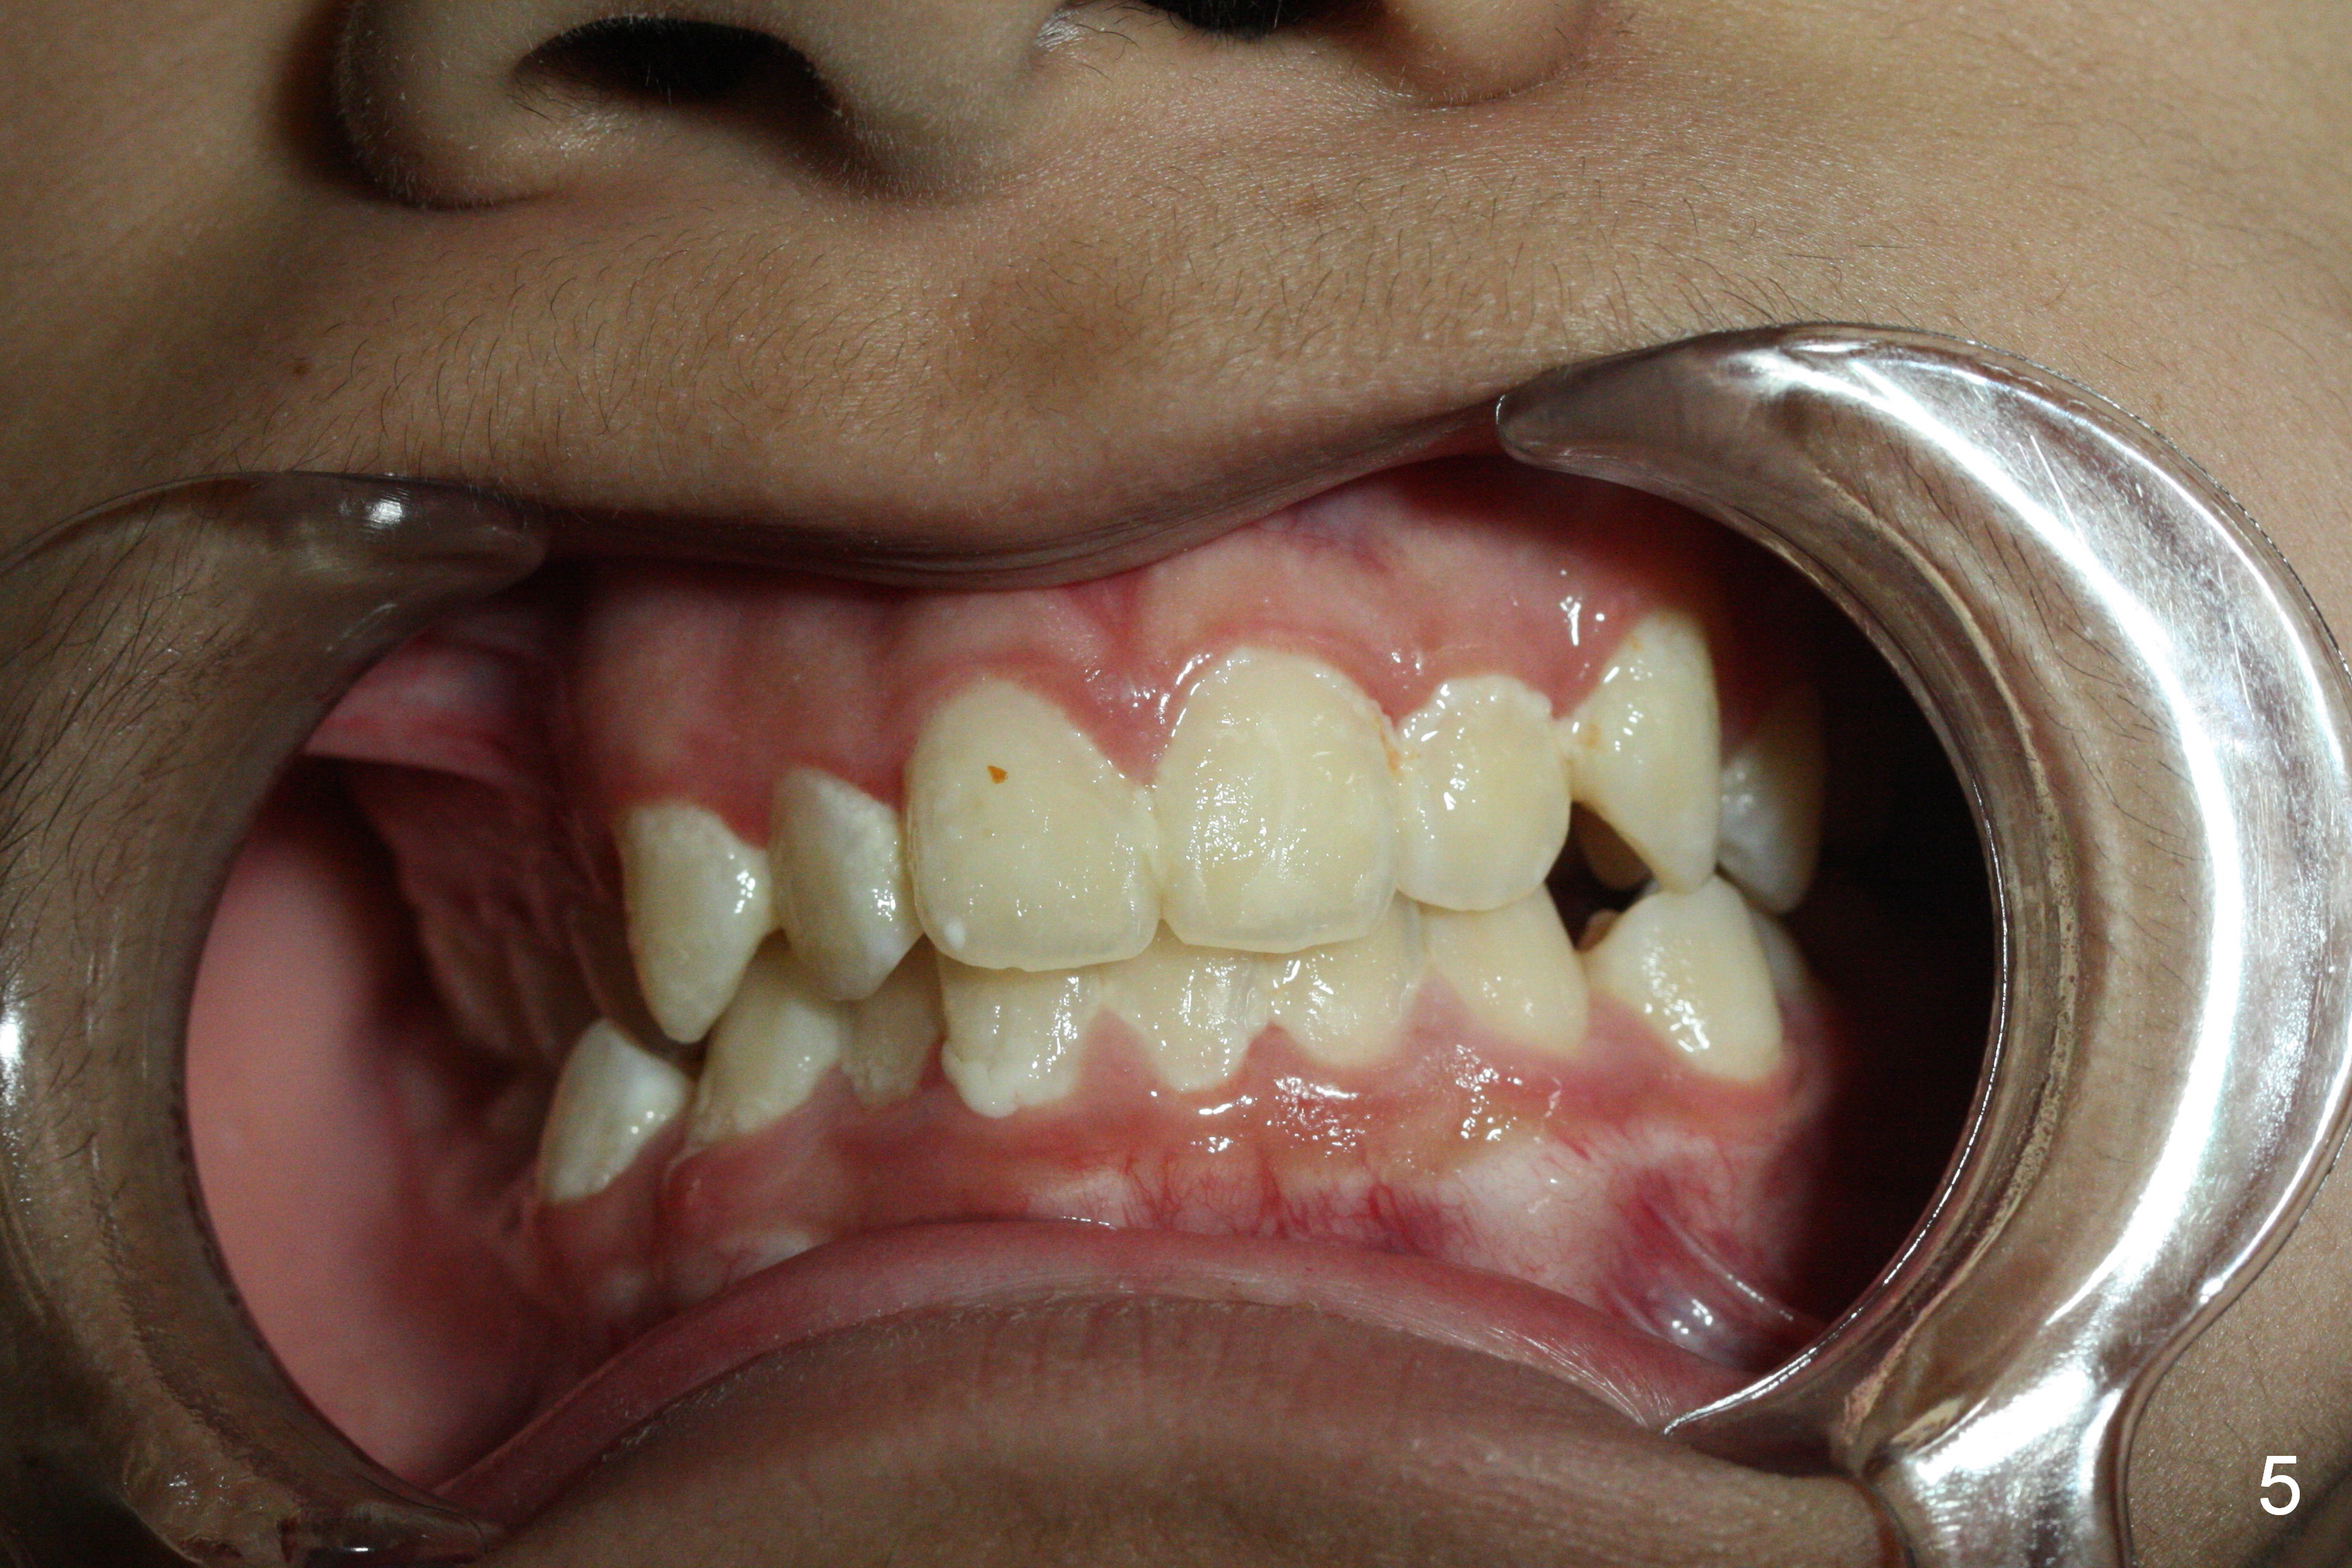

A 13-year-old man's malocclusion has two major components: upper midline deviation (Fig.2,5) and severe crowding (Fig.2,5-7).  His mother resists extraction, in spite of facial profile analysis (Fig.4,4').  A second obstacle to orthodontic treatment is his poor oral hygiene (Fig.5-7).  Before prophylaxis on Monday, can we decide together whether his oral hygiene has been improved drastically over the weekend?  If not, banding and bracketing will be canceled on Tuesday.

The advantage of extraction is that there is an opportunity to move the upper deviated midline to the right when UR4 space is available.

In addition to compromise of the facial profile, orthodontic treatment without extraction will move the roots of the anterior teeth out of their supporting alveolus.  There will be higher chance of the buccal gingival recession when he grows older.  Explain the above to his mother in layman's term.